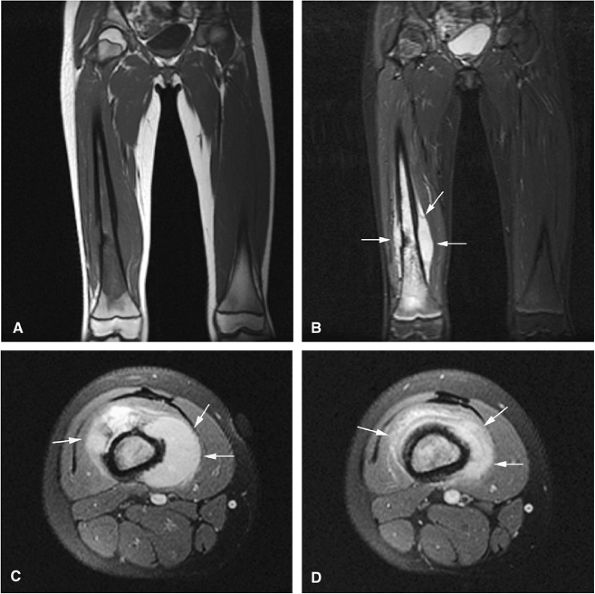

FIGURE 14-80 ● (A) Proton density axial image of a 12-year-old boy with an extensive intermediate-signal soft-tissue abnormality representing extensive round cell infiltrate and edema into the surrounding muscle compartments from a Ewing sarcoma of the femur. (B) Same proton density study after two cycles of chemotherapy, with dramatic shrinkage of the tumor margins (arrow). (C) Photograph of the amputated specimen, with arrow indicating the same tumor margin seen in B. (D) Gross macrosection of same specimen, with extracortical tumor margin indicated by arrow.

There is usually a substantial soft-tissue component associated with Ewing sarcoma, which is well evaluated with MR imaging. Since MR imaging provides excellent delineation of soft tissues, the extent of muscular and neurovascular involvement in extraosseous Ewing sarcoma can be accurately assessed.

In addition, Ewing sarcoma originating in bone marrow can be identified in the early stages, before cortical erosion and periostitis have developed.

MR imaging has been used after chemotherapy to more accurately define tumor margins and assess the interval decrease in adjacent peritumoral edema.